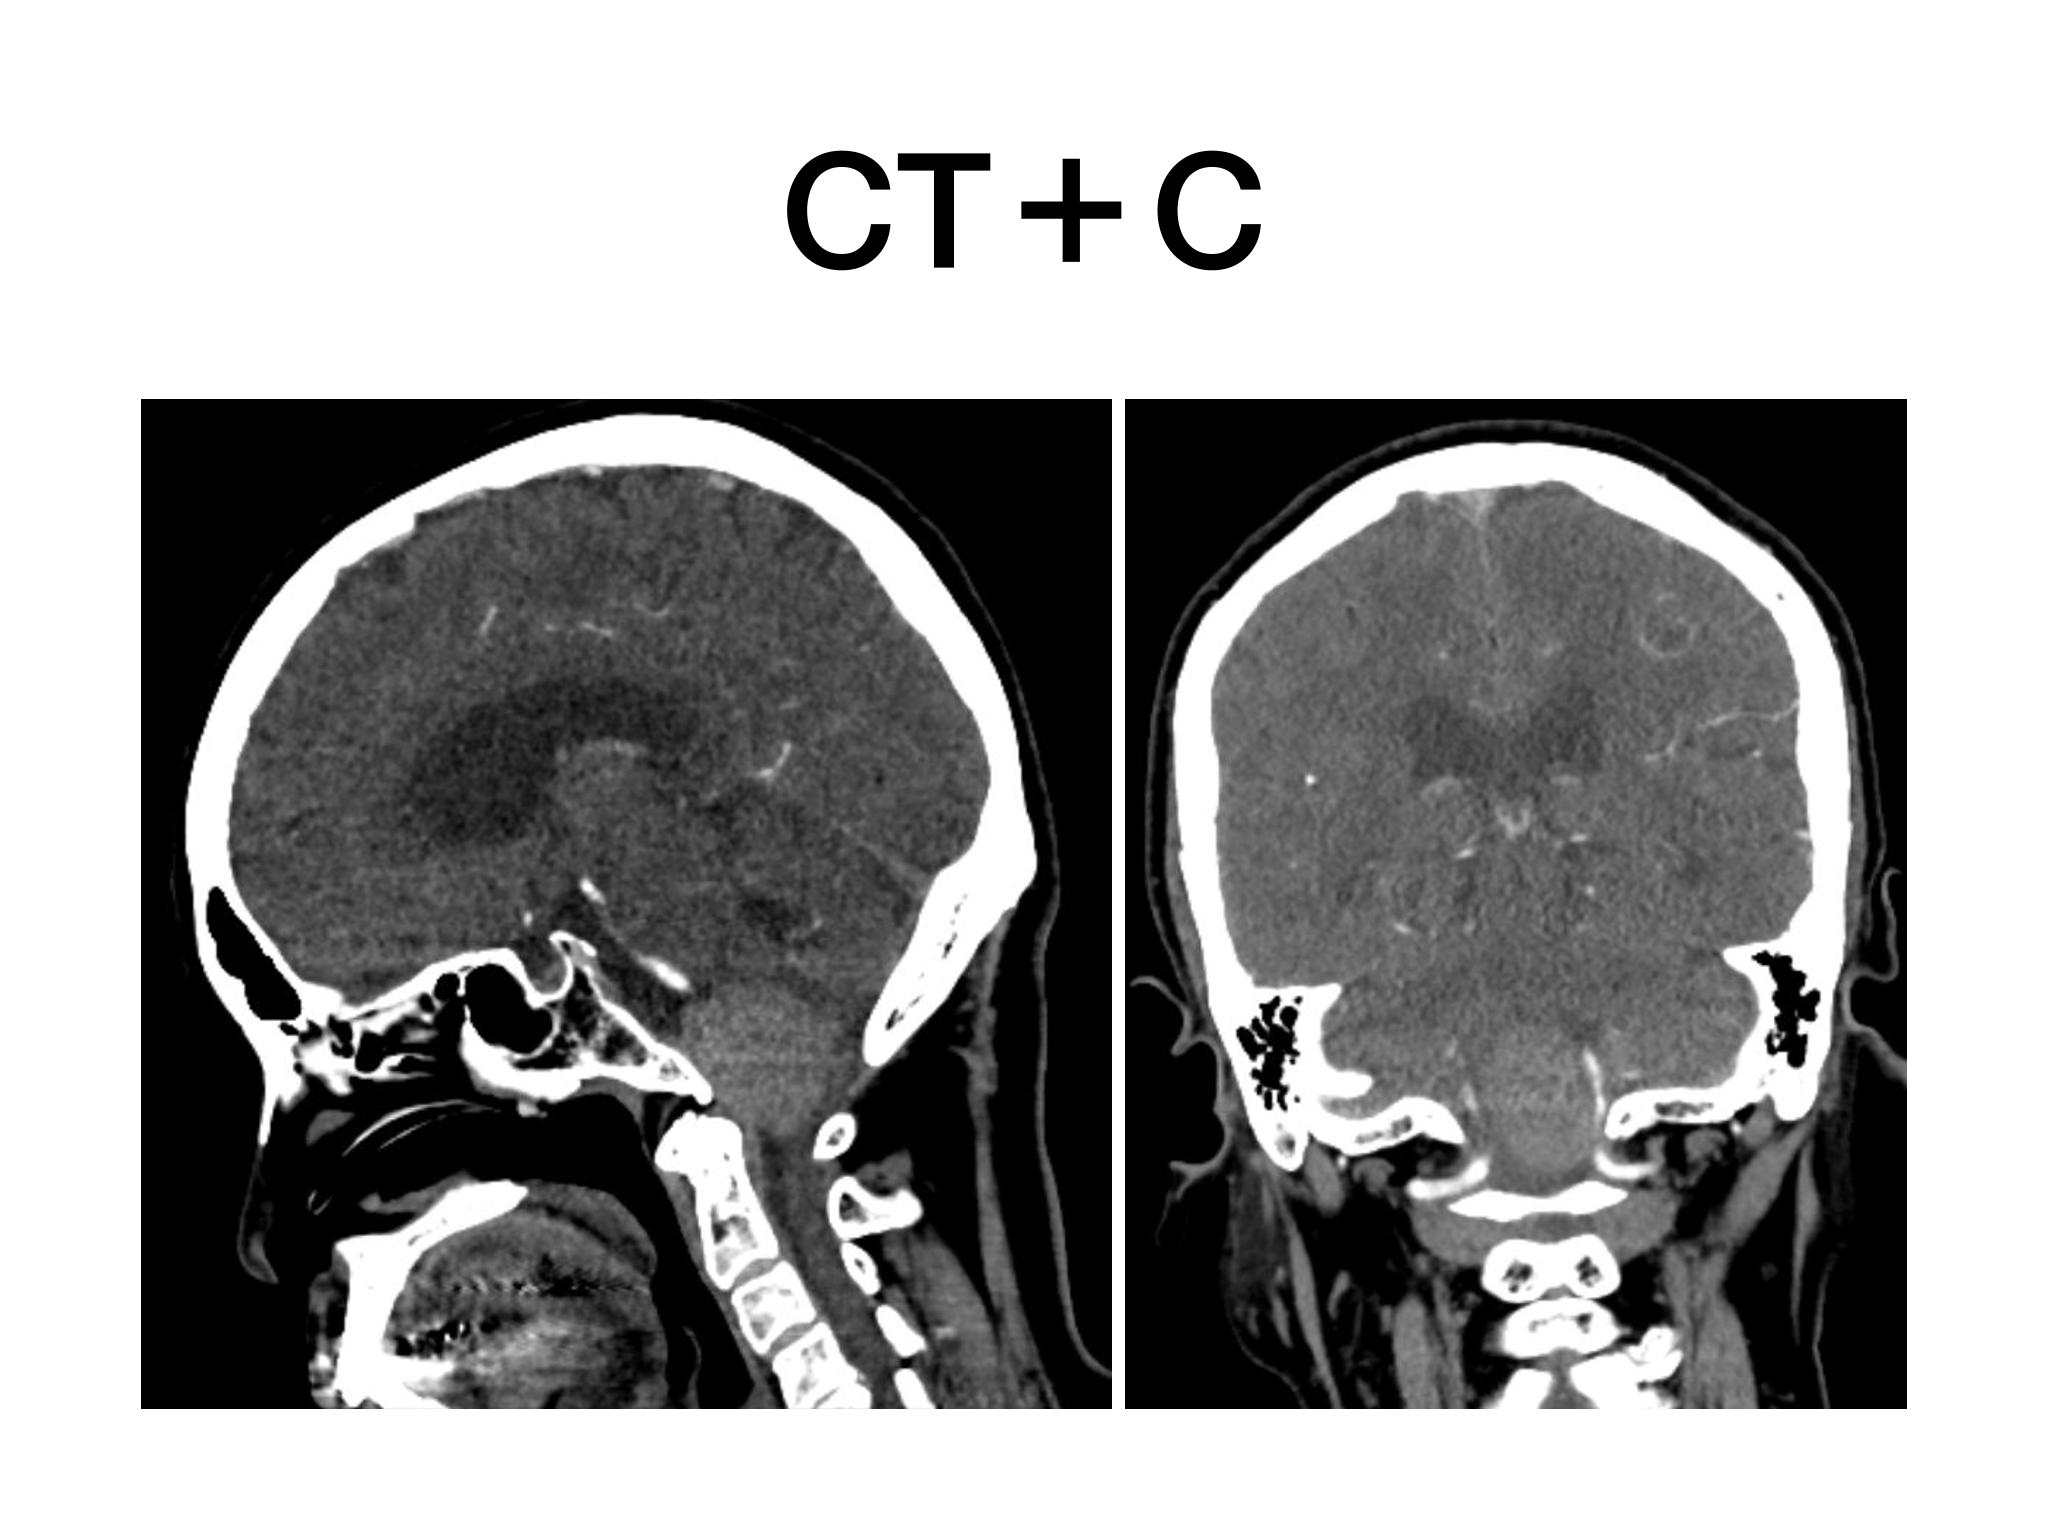

汇报一例后颅底肿瘤手术。为枕骨大孔巨大腹侧型脑膜瘤,该患者高龄,同时合并肺Ca,术前2周急性加重,枕骨大孔疝前期表现,术前已有延髓压迫及后组颅神经麻痹表现。经详细评估后采用远外侧经髁窝入路,最大化显露,重点保护延髓、后组颅神经,尽可能“零骚扰”。术中肿瘤质地韧,血供一般,与肿瘤上极与后组颅神经黏连紧密,最终99%切除,残留约1%,术后顺利康复出院,无新发症状,为后续进行肺部病变化疗创造有利条件。